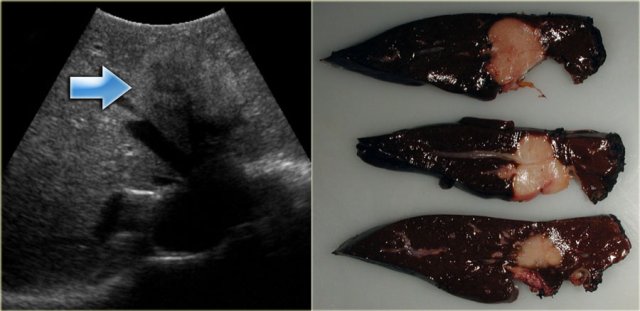

Study the image on the left.

There is focal dilatation with intermixing strictures of the bile ducts in segment IV (arrow).

The other bile ducts and the choledochal duct are normal.

In some of the cases of Caroli disease the imaging findings may simulate a cystic neoplasm as is seen in the case on the left.

This case was originally diagnosed as a biliary cystadenoma.

However, the gross specimen demonstrates dilated bile ducts and ductal plate malformation was present microscopically.